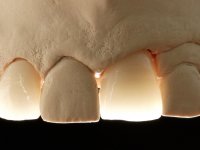

Treatment began with re-preparation of the cast post and core, with the purpose of placing the cervical finishing lines with an intra-sulcular location and simultaneously making a suitable temporary crown. With a very simple orthodontic treatment, the diastema was closed between the upper central incisors, and this position was stabilized with a wire placed on the palatal surface of the central, functioning as containment. Later, a slow orthodontic traction of tooth 2.2 was attempted, in order to reduce, although very slightly, the vertical bone loss in this area. At the end of the traction, tooth 2.2 was extracted and the area was provisionally rehabilitated with a composite resin crown bonded to the adjacent teeth. A dental implant was placed in the area of tooth 2.2 and the temporary crown was again bonded to resin, provisionally rehabilitating the patient during osseointegration. In tooth 1.3 a gingivectomy with an electric scalpel was performed, with the intention of raising the cervical level of 1.3 achieving greater harmony with tooth 2.3. Stabilized soft tissues were impressed using the open tray technique with putty and light addition silicones. Collection of the color of both the dental component and soft tissues was done by the ceramist in the office. In the laboratory, the impressions were transferred to plaster and gave origin to work models that were properly analyzed. It was decided to assemble a metal-ceramic abutment screwed onto the implant. This abutment was cast with a noble alloy and subsequently coated with coronary and gingival ceramics. Due to the inclination of the implant, the screwing inevitably conditioned the exit of the screw hole through the vestibular surface. In order to conceal this situation, the design of the abutment has already been conceived with the intention of accommodating on the vestibular surface the bonding of a feldspathic veneer. This abutment was tested in the mouth and adjustments were made in the gingival ceramic component. Its adaptation to the soft tissues was done in a subtractive way, with a drill, as well as additive, adding resin composed of gingival tonality.

This addition of resin would guide the ceramist in the final placement of the gingival tonality ceramic. The crown that would rehabilitate tooth 1.3 was cemented in this test session with glass ionomer cement, reinforced with composite resin. Once the laboratory work was finished on the veneer for tooth 1.2, the abutment, and the veneer for the implant, this was bonded in the mouth, after placement of the absolute insulation. The work completely satisfied the patient. For eight years, the patient had periodical check-ups, and was pleased with the treatment, but also began to show interest in an aesthetical intervention on the upper central incisors. Once the second phase of our intervention was decided, dental preparation of teeth 1.1 and 2.1 was performed for the placement of two feldspathic veneers. Particular care was taken in the distal inter-proximal preparation adjacent to the abutment of the implant.

The axis of insertion of the veneer in relation to the abutment was very carefully evaluated. The feldspathic veneers were prepared in the laboratory and then bonded to the mouth after placing absolute insulation. One year later, we began our third phase of treatment, after the veneer in tooth 2.1 fractured. A dental preparation was done on the bonded veneer, seeking to extend the distal inter-proximal interface more to the palate. The objective would be to move the veneer to a more palatine contact point. Preparation of tooth 1.2 was limited to creating an insertion axis. After preparation, the total crown and laboratory veneer were bonded to the mouth. First, the crown was bonded using a relative insulation with Teflon, later the veneer was bonded after the absolute insulation placement. In the crown, I used this type of insulation to avoid the use of staples. It would be difficult to apply due to the shape and size of the tooth, and would also be aggressive to the soft tissues. After bonding procedures, the occlusal integration of the work was evaluated.